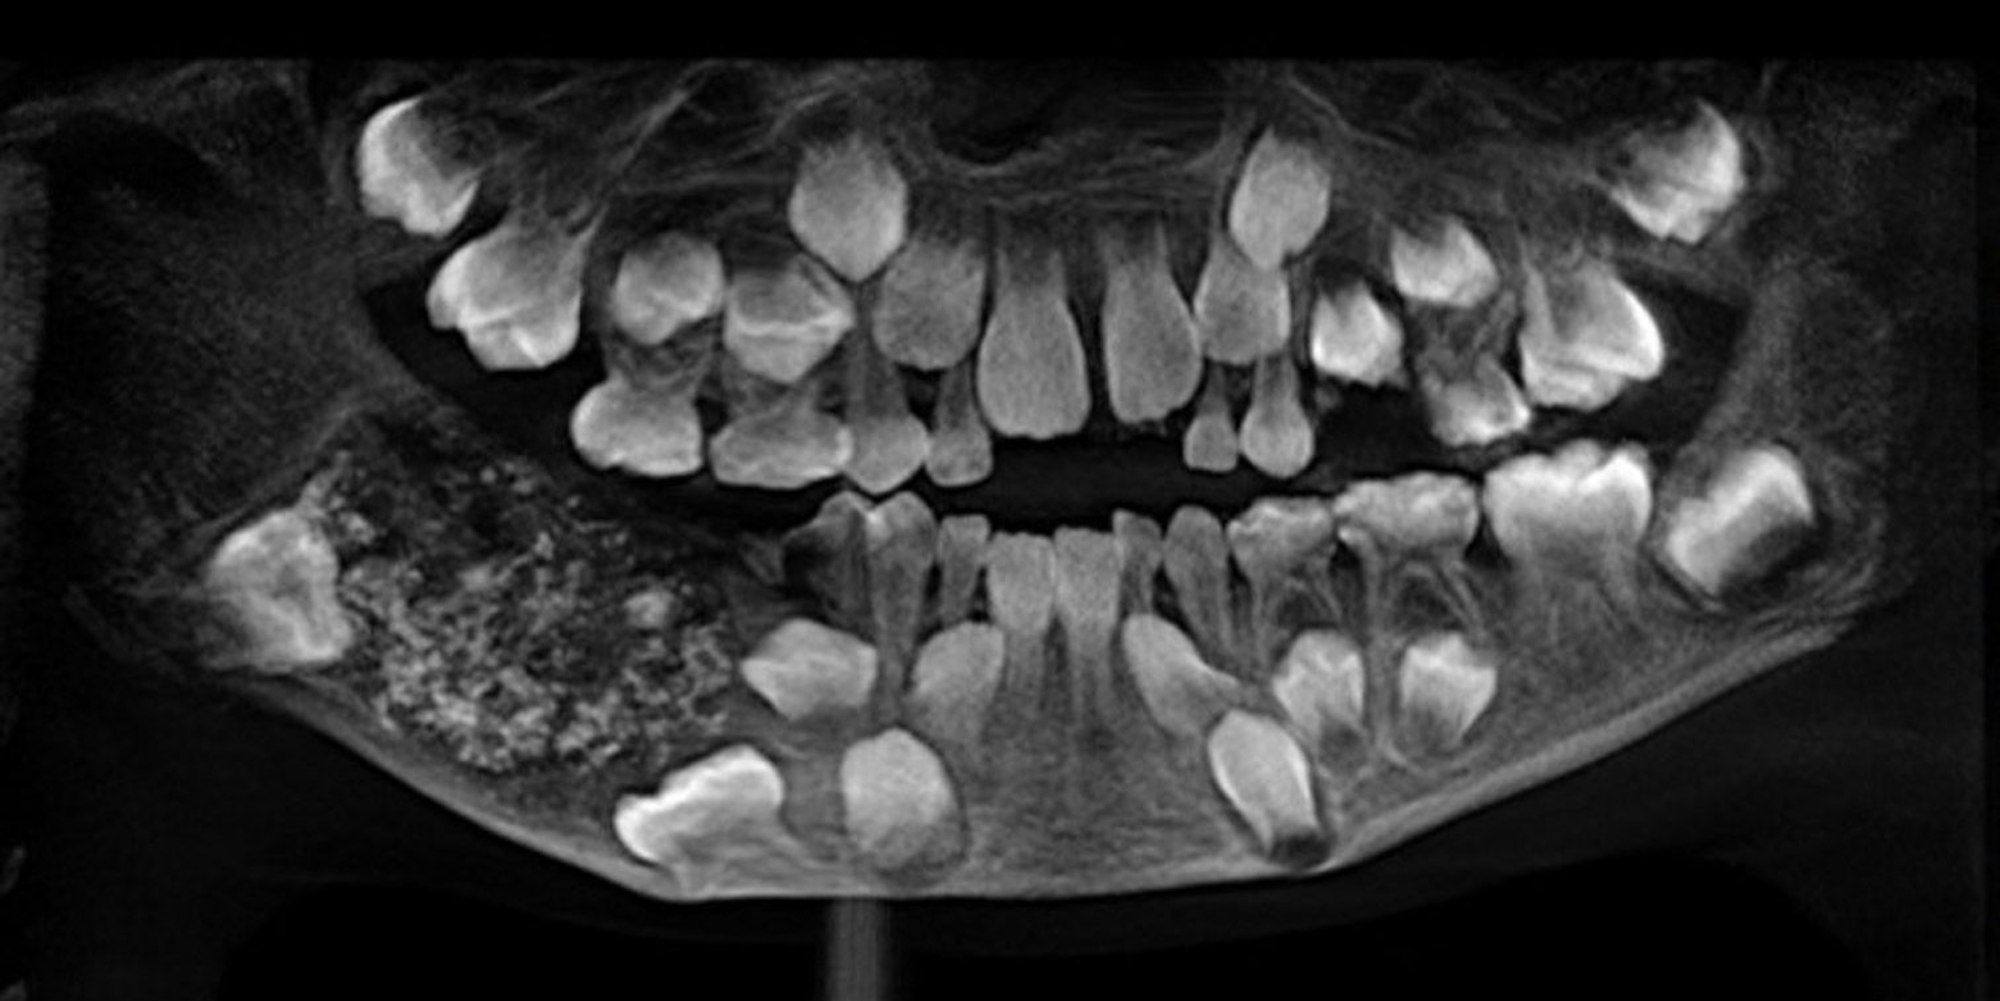

Indien, Chennai: Das Röntgenbild des Saveetha Dental College and Hospital zeigt eine ungewöhnlich große Zahl an Zähnen im Mund eines Siebenjährigen. Bei allen habe es sich um Zähne gehandelt, da sie Wurzel, Krone sowie Zahnschmelz aufwiesen.

Neu Delhi – Eine ungewöhnlich große Zahl an Zähnen haben Ärzte im Südosten Indiens eigenen Angaben zufolge aus dem Kiefer eines Jungen herausoperiert. „Wir haben 526 Zähne in der Größenordnung von 0,1 Millimeter bis 15 Millimeter entfernt“, sagte Pratibha Ramani, Chefin der Fachabteilung im Krankenhaus Saveetha Dental College and Hospital in Chennai, am Freitag. Alle Zähne hätten Wurzel, Krone sowie Zahnschmelz gehabt. Ramani zufolge ist dies der bisher größte dokumentierte Fund von Zähnen im Mund eines Menschen.

Der Siebenjährige habe zuvor über Kieferschmerzen und Schwellungen geklagt, ohne dass die im rechten Unterkiefer versteckten und nicht sichtbaren Zähne entdeckt worden seien, sagte Ramani weiter. Demnach litt er an einem sogenannten Odontom, einer gutartigen Geschwulst, die viele rudimentäre Zähne enthalten kann. Ungewöhnlich ist jedoch die Zahl. 2014 waren einem Teenager im westindischen Mumbai nach Angaben des Krankenhauses 232 Zähne entfernt worden.

Röntgenbilder des Krankenhauses in Chennai zeigen eine Ansammlung von Zähnen. Der Junge habe nach dem Eingriff nun eine „gesunde Anzahl von 21 Zähnen“ und sei drei Tage nach der Operation entlassen worden. Der fünfstündige Eingriff erfolgte bereits am 11. Juli, wie das Krankenhaus weiter mitteilte. Das Team um Ramani habe danach aber erst einmal alle entfernten Stücke analysiert, bevor es mit dem Fund an die Öffentlichkeit ging. Die 526 Zähne hatten demnach ein Gewicht von insgesamt 200 Gramm. (dpa)